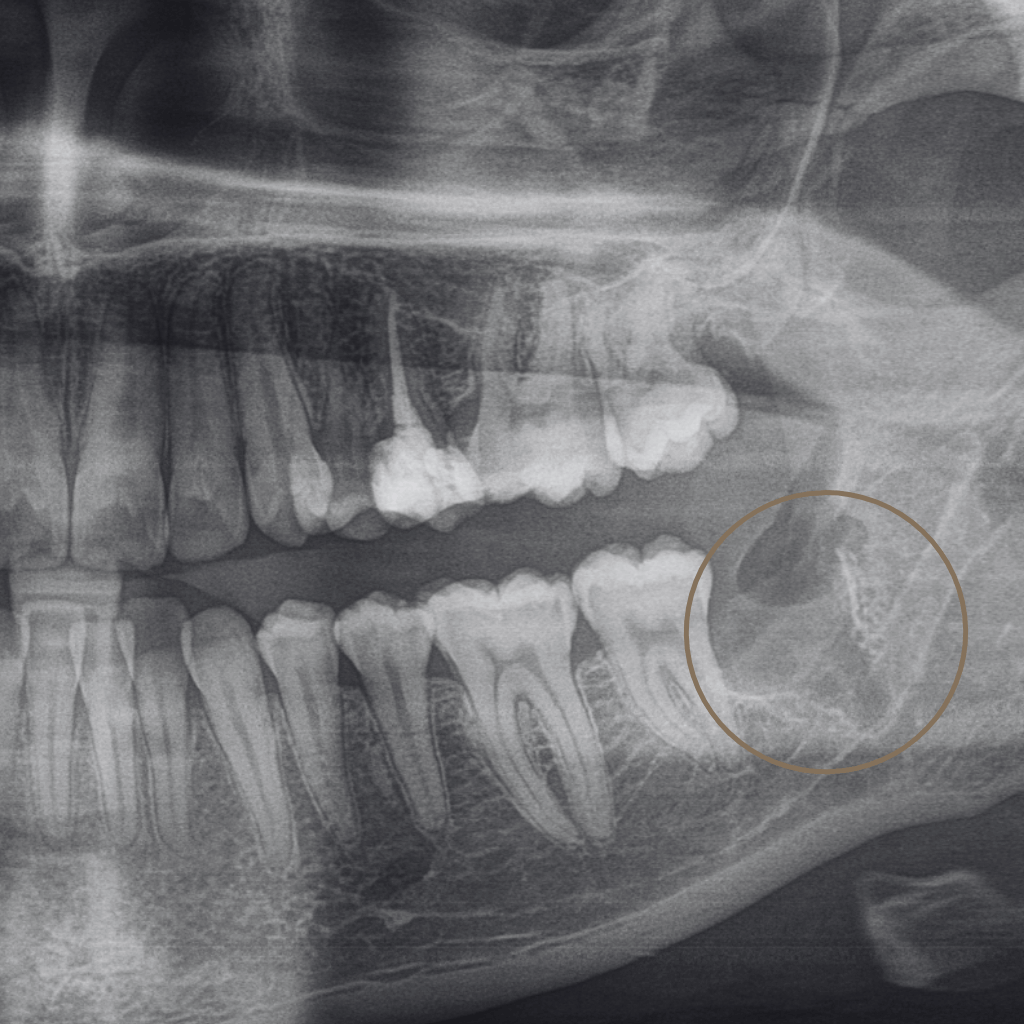

Екстракцията е хирургична процедура, при която зъбът се отстранява, когато неговото запазване не е възможно или би компрометирало цялостното орално здраве. В Aesthetico екстракциите се извършват след внимателна оценка и с ясна цел – лечение, облекчаване на болката и създаване на стабилна основа за последващи стъпки.